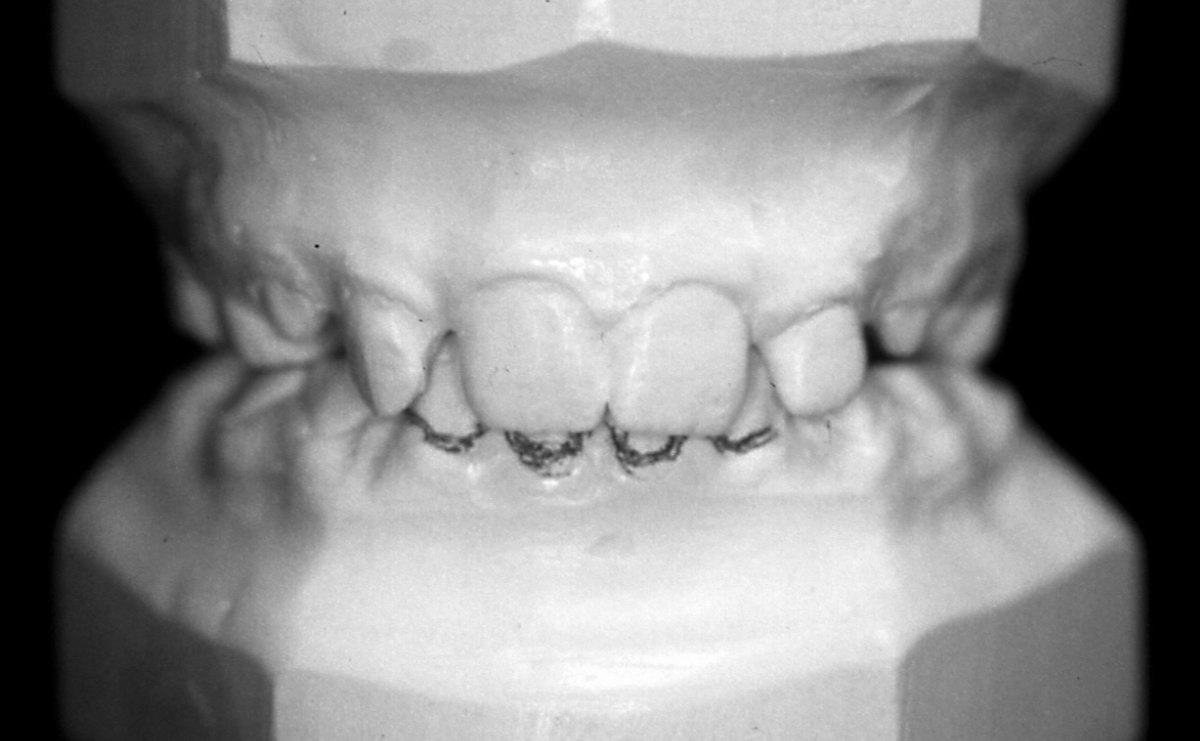

Наскоро излезе книгата на д-р Мишел Монто Нашите зъби - портал към здравето. Д-р Татяна Тасева, медицински консултант на книгата, любезно се съгласи да отговори на няколко въпроса. Защо книгата не е това, което изглежда; как мъдростта на зъбите (дентософията) може да промени целия живот на човека – вече и в България; как психоемоционалното състояние зависи от хармонията в устата и още можете да прочетете тук.

От баланса на нашите зъби зависят психичното здраве и емоционалният ни комфорт (интервю)